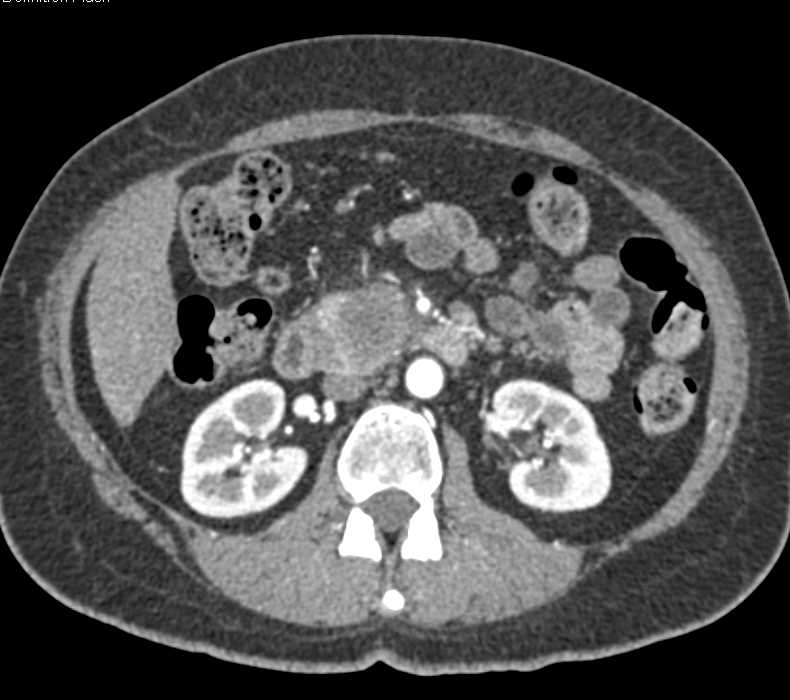

Adenocarcinoma of the Head of the Pancreas